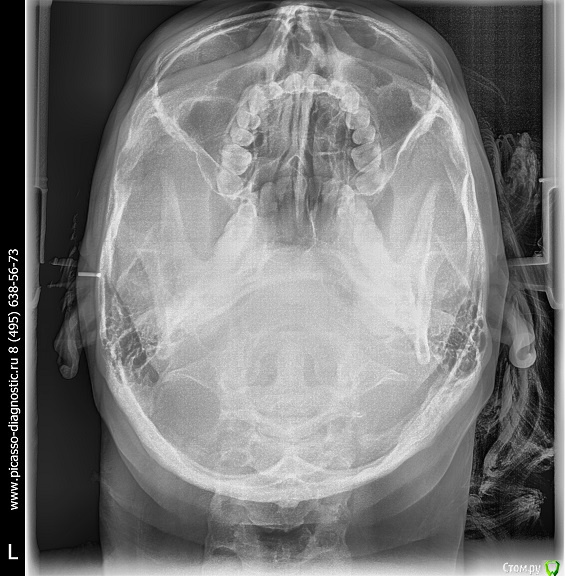

Arseny0111 Опубликовано 27 сентября, 2015 Поделиться Опубликовано 27 сентября, 2015 (изменено) Здравствуйте,в ходе драки получил удар,в верхнюю челюсть,сразу же не значительно сменился прикус и искривилась носовая перегородка.Есть ли на снимках отклонения от нормы?трещина?и т.д.Что с этим делать к кому обращаться?Из исследований дополнительно имеется МСКТ(3D)Спасибо. Изменено 27 сентября, 2015 пользователем Arseny0111 Ссылка на комментарий

Arseny0111 Опубликовано 1 октября, 2015 Автор Поделиться Опубликовано 1 октября, 2015 Здравствуйте,в ходе драки получил удар,в верхнюю челюсть,сразу же не значительно сменился прикус и искривилась носовая перегородка.Есть ли на снимках отклонения от нормы?трещина?и т.д.Что с этим делать к кому обращаться?Из исследований дополнительно имеется МСКТ(3D)Спасибо.Уважаемые доктора,помогите пожалуйста.Неужели нет компетентных специалистов в этой области? Ссылка на комментарий